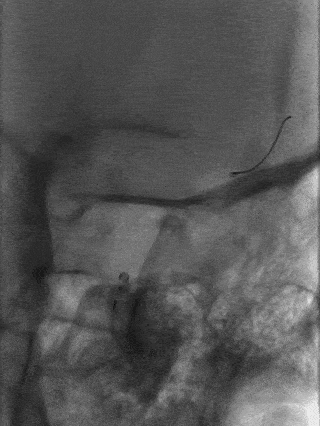

术中耗材

8F 导引导管

5F 单弯导管

0.035" 150cm超滑泥鳅导丝

6F 125cm 中间导管

Marksman™ 导管0.014" 200cm 微导丝Pipeline™ Flex血流导向密网支架 PED-325-25

手术过程微导管到位: